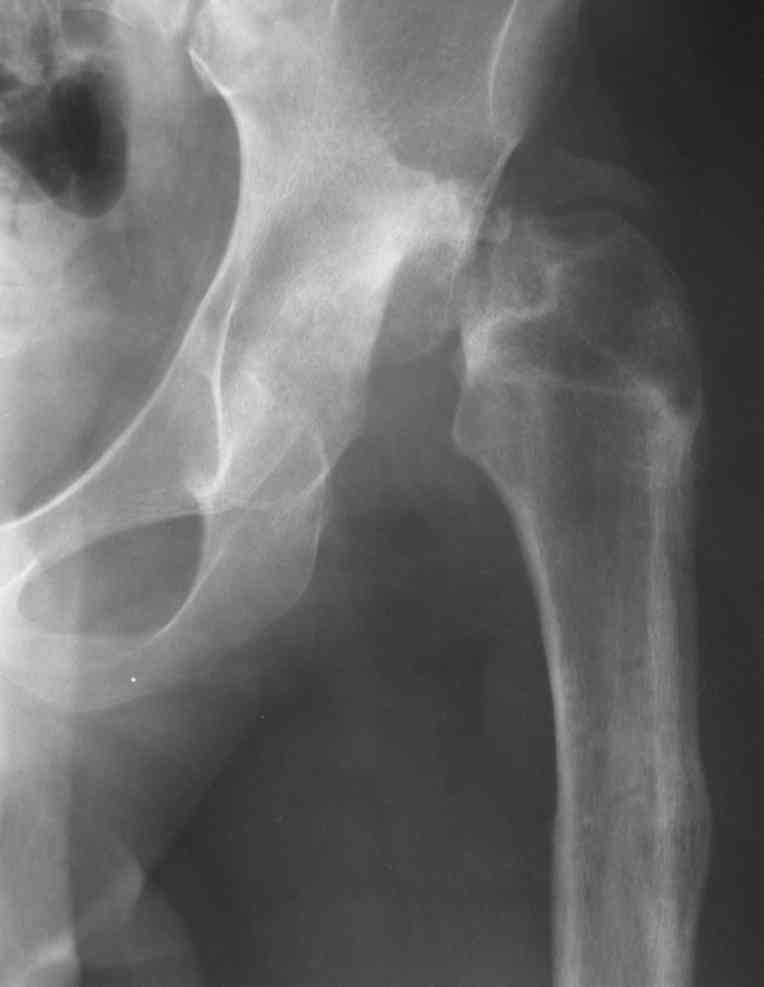

Moghno i tak kak sdelali my: pelvic support + tibial and equinus correction .

Слайд 1

Слайд 2

Слайд 3

Слайд 4

Devushka predstavlennaya na snimke nachala s LLD 9 cm, valgus deformation of the tibia, huge Trendelenburg( vidno na snimke).

Seichas : no LLD ,no Trendelenburg, reasonable hip motion.A samoe glavnoe ei ne predstoit kaghdye 10-15 let delat revision THR.